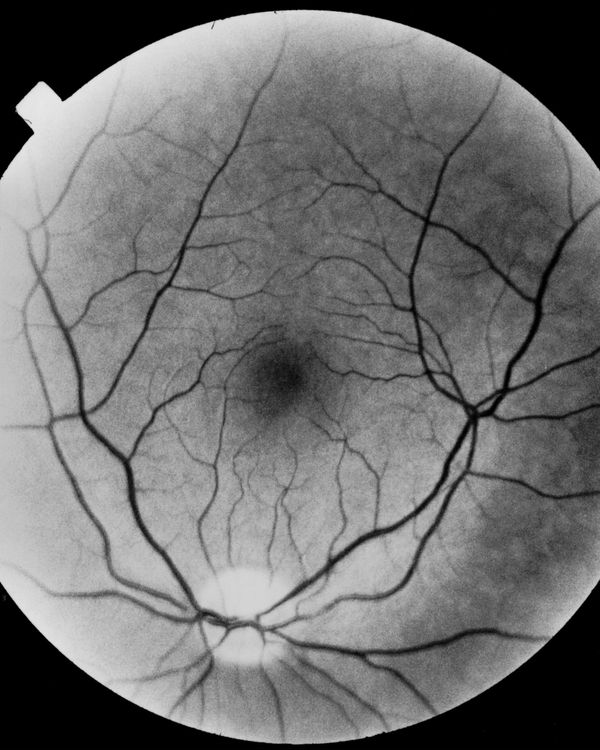

A visual narration of blindness is closely linked to memory, although the sight ceases, what remains is the entirety of the experiences that time offers us to the extent that we exist.

This visual nature of the past that gives shape to our memories, does not fit, in appearance, with blindness, yet, I wanted to probe this aspect, trying to tell the fear of losing sight.

Hence, starting from this contradiction only apparently irresolvable, the search for a visual narration of the fear of losing sight is closely linked to memory, although the sight ceases, what remains is the entirety of the experiences that time offers us to the extent that we exist and existence is nothing more than a continuous encounter between us, the world and what goes beyond us.